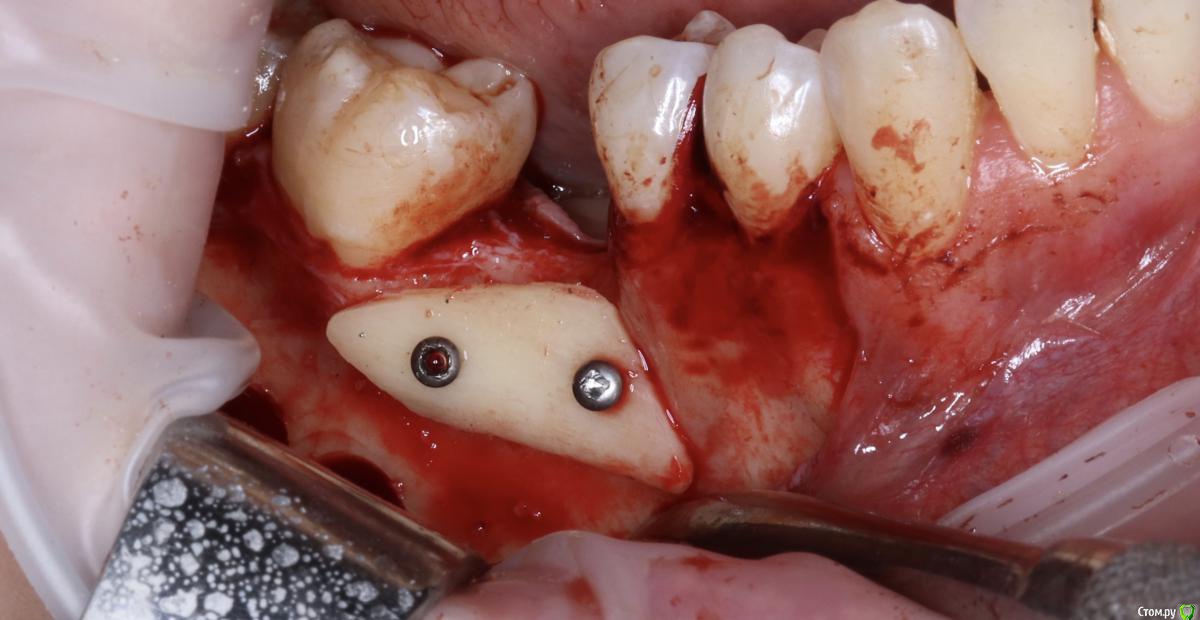

Александр07 Опубликовано 21 августа, 2020 Поделиться Опубликовано 21 августа, 2020 Коллеги добрый день, решил углубиться в тематику костных пластин по Кюри, определенные знания и некоторый опыт есть, небольшой, хотел поделиться последней работой, если какие то советы /замечания есть с удовольствием выслушаю 8 Ссылка на комментарий

Kev Опубликовано 25 августа, 2020 Поделиться Опубликовано 25 августа, 2020 толстый очень ламинат. а так все хорошо )Олег, Вы сосиску сделали бы? Ссылка на комментарий

Bier Опубликовано 27 августа, 2020 Поделиться Опубликовано 27 августа, 2020 Олег, Вы сосиску сделали бы?да 1 Ссылка на комментарий